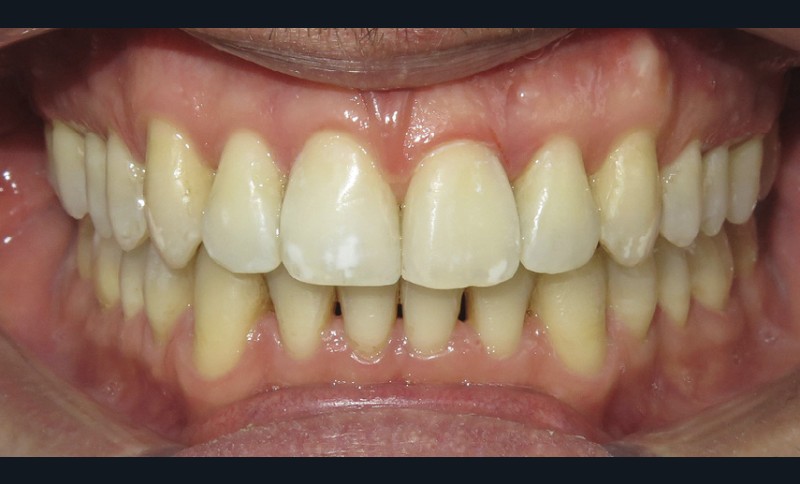

Diagnostic (fig. 1a-i)

Le patient consulte initialement pour des défauts d’alignement. L’examen clinique confirme l’existence d’un encombrement antérieur bimaxillaire, mais révèle aussi la présence d’une Classe II dentaire sévère, d’une exoclusion de la 27 et de troubles parodontaux (peu ou absence de papilles inter-dentaires). Sur le plan squelettique, le patient est relativement équilibré avec un profil harmonieux.